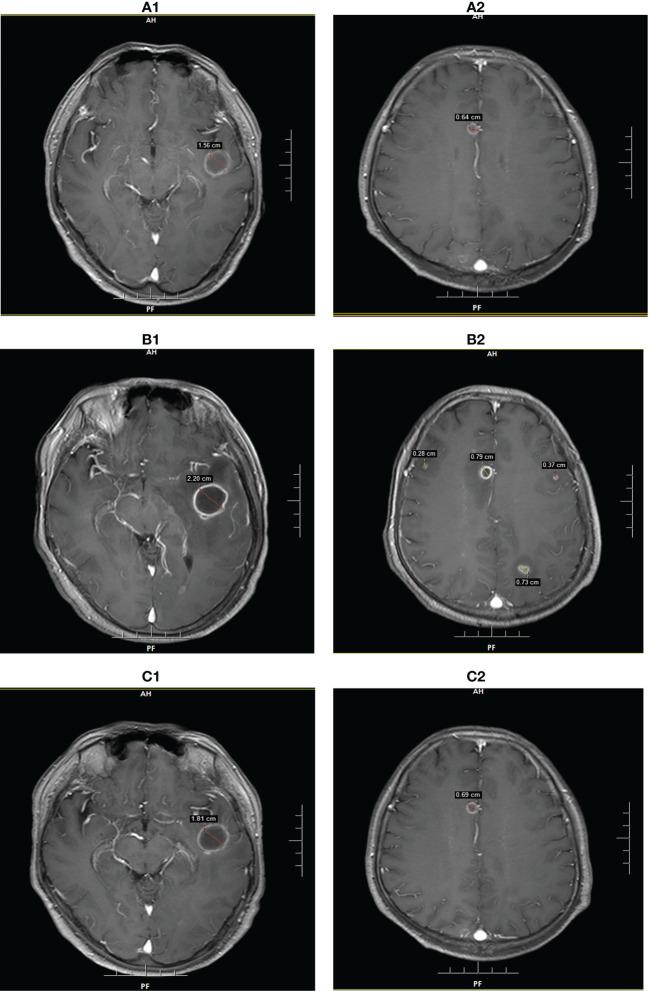

Central nervous system (CNS) infections in adults are rare because of normal immunity and the existence of the blood brain barrier, which prevents the invasion of pathogenic microorganisms. Liver transplant recipients are at an increased risk of opportunistic infections (OI) due to immunosuppressive therapy compared to those with normal immunity. Early diagnosis and timely implementation of treatment are critical for the successful treatment of these infections. We present two cases of intracerebral OI after orthotopic liver transplantation (OLT), with different clinical presentations. Patient 1 presented with epileptic seizures, mainly manifested as unresponsiveness, unconsciousness, and coma complicated with involuntary limb twitching. Patient 2 presented with a consciousness disorder, mainly manifested as unclear consciousness content, poor orientation, calculation power, and logical ability. Next-generation sequencing (NGS) examination of the cerebrospinal fluid confirmed human herpesvirus 6 B (HHV-6B) infection in patient 1 and intracranial Aspergillus infection in patient 2. Intracranial OI has insidious onset and atypical clinical manifestations. NGS can allow for the proper diagnosis and monitoring of the effects of treatment.

成人中枢神经系统(CNS)感染较为罕见,这是因为人体具有正常的免疫功能和血脑屏障,后者可阻止致病微生物的侵袭。与具有正常免疫功能的人群相比,肝移植受者由于免疫抑制治疗而面临更高的机会性感染(OI)风险。早期诊断和及时实施治疗对于成功治疗这些感染至关重要。我们报告了两例肝移植后颅内 OI 病例,其临床表现不同。患者 1 表现为癫痫发作,主要表现为反应迟钝、意识不清和昏迷,伴有不自主的肢体抽搐。患者 2 表现为意识障碍,主要表现为意识内容不清、定向力差、计算力和逻辑能力差。对脑脊液进行下一代测序(NGS)检查后,患者 1 被确诊为人疱疹病毒 6B(HHV-6B)感染,患者 2 被确诊为颅内曲霉菌感染。颅内 OI 的发病隐匿,临床表现不典型。NGS 可实现正确诊断和治疗效果监测。